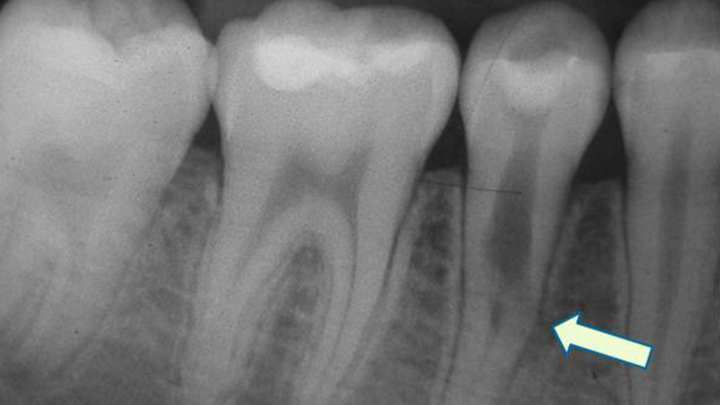

Did you know teeth can just be resorbed? I didn't!

But one of my upper molars, which is super visible when I smile, is being resorbed. Resorption happens more in people who've had orthodontia, and this tooth is one of the ones next to the teeth that got pulled & so would have moved the most when I had braces in Jr High.

NOTE: The tooth image in the header isn't my specific x-ray - I didn't have the foresight to ask for a copy of my x-rays, so I pulled that image from the frankly terrifying amount of x-ray imagery of tooth resorption online.